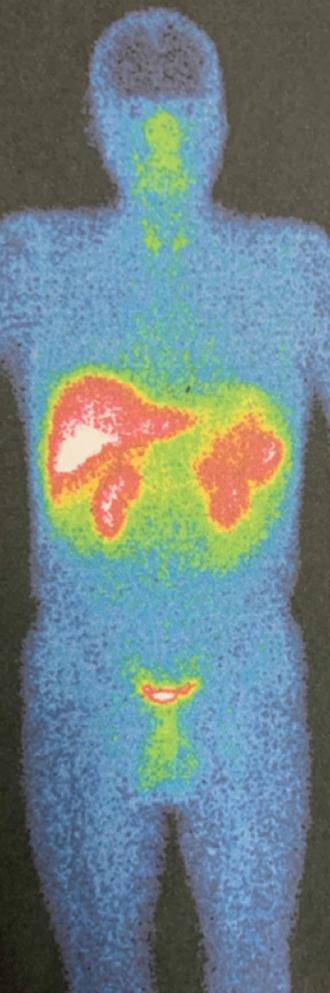

También se lleva a cabo un centellograma con octreotida-Tc-99m que muestra una lesión hipercaptante en el lóbulo derecho del hígado (Fig. 3). No se encuentran áreas anormales en el resto del cuerpo entero rastreado. Se complementa el protocolo con tomografía computada por emisión de positrones (PET) de cuerpo entero, encontrando una lesión hepática en el segmento VI-VII, hipodensa, con aumento de metabolismo (Fig. 4), y aumento difuso de metabolismo en el esófago y el cuerpo gástrico.

Figura 3 Gammagrafía. Corte coronal que demuestra un aumento de la captación en el lóbulo hepático derecho.

En algunos trabajos se ha reportado que la gammagrafía/centellografía resulta ser más sensible que cualquier otro método de imagen para la identificación de un gastrinoma10. Localiza los NET de manera exitosa hasta en un 78-86% y se ha convertido en el estudio de imagen de elección para los pacientes con sospecha de gastrinoma7. Por otra parte, la PET ha revolucionado en los últimos años los protocolos de estudio para buscar neoplasias, gracias a su capacidad de visualizar actividad metabólica. Ambos estudios fueron aplicados en este paciente y sus resultados corroboraron que se trataba de un NET hepático primario, descartando de manera contundente una posible lesión secundaria en otro órgano. Posterior a la realización de pruebas séricas y al encontrar unos valores de gastrina extremadamente altos, se concluyó el diagnóstico de gastrinoma hepático primario.